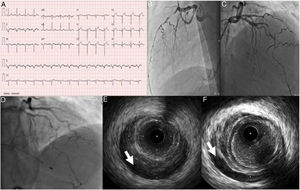

Uma semana após o evento agudo, foi repetida coronariografia e realizada tomografia de coerência ótica (OCT), que confirmou uma boa aposição e expansão dos stents previamente implantados e a presença de trombo vermelho intrastent mais evidente na porção médio‐distal do vaso, sem condicionar, no entanto, uma obstrução significativa do lúmen (Figura 2).

O doente teve alta ao sétimo dia de internamento sob estratégia antitrombótica tripla com a apixabano 2,5mg bid; clopidogrel 75mg id e AAS 100mg id, suspendendo o apixabano aos três meses após o evento. Aos seis meses após o episódio agudo, o doente mantém‐se assintomático, sem recrudescência anginosa, mostrando o follow‐up angiográfico com imagem intracoronária aos seis meses stents bem apostos, desaparecimento do trombo vermelho e fluxo TIMI 3.